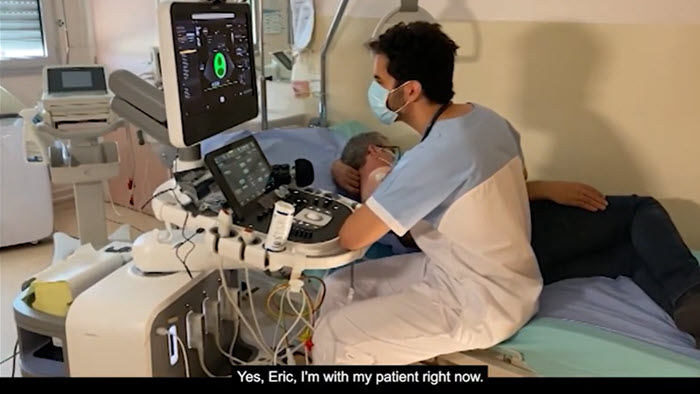

Collaboration Live

Watch how Dr. Saloux, cardiologist at the CHU de Caen in Normandy, France, uses Collaboration Live to enable access to care via tele-medicine with ultrasound, remotely consulting with colleagues in cardiology departments at satellite hospitals in Normandy, France, transforming the delivery of healthcare.